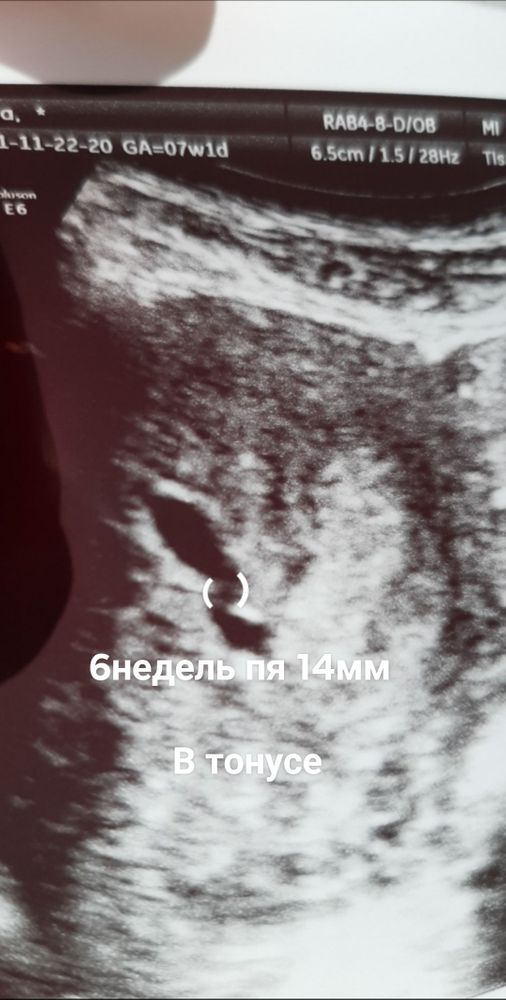

7недель динамика пя

Светлана , должна здать анализи в пониделник . Тест не делала. Меня уже на учёт поставили. Врач прописал таблетки чтоб снять тонус. Прочитала что у многих так было

Светлана , у меня в москве сестра она показала фото узи своему узисту она сказалв что тонус и думает что емриона тоже видно. После завтра иду на узи самаму лутшему узисту в грузие. Сечас принемаю утрожестан и магни б6.